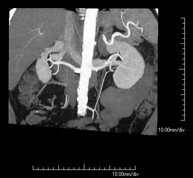

- Angio-TC arterias renales  Prueba diagnóstica no invasiva que consiste en el estudio de las arterias renales obteniendo imágenes de alta definición anatómica mediante el empleo de un equipo de TC (Tomografía Computarizada) y de contraste yodado. La calidad de las imágenes permite realizar reconstrucciones en 2D y 3D gracias a estaciones de trabajo especializadas en el estudio arterial. Esta prueba está indicada, por ejemplo, en aquellos pacientes que sufren de HTA refractaria al tratamiento, en pacientes con lesiones renales para tener un mapa "vascular" pre-quirúrgico, etc. Prueba diagnóstica no invasiva que consiste en el estudio de las arterias renales obteniendo imágenes de alta definición anatómica mediante el empleo de un equipo de TC (Tomografía Computarizada) y de contraste yodado. La calidad de las imágenes permite realizar reconstrucciones en 2D y 3D gracias a estaciones de trabajo especializadas en el estudio arterial. Esta prueba está indicada, por ejemplo, en aquellos pacientes que sufren de HTA refractaria al tratamiento, en pacientes con lesiones renales para tener un mapa "vascular" pre-quirúrgico, etc.

- Angio TC d'artèries renals Prova diagnòstica no invasiva que consisteix en l'estudi de les artèries renals amb l'obtenció d'imatges d'alta definició anatòmica mitjançant l'ús d'un equip de TC (Tomografia Computaritzada) i contrast iodat. La qualitat de les imatges permet realitzar reconstruccions en 2D i 3D gràcies a estacions de treball especialitzades en l'estudi arterial. Aquesta prova està indicat en aquells pacients que pateixen HTA refractària al tractament, en pacients amb lesions renals que tenen un mapa vascular prequirúrgic, etc. Prova diagnòstica no invasiva que consisteix en l'estudi de les artèries renals amb l'obtenció d'imatges d'alta definició anatòmica mitjançant l'ús d'un equip de TC (Tomografia Computaritzada) i contrast iodat. La qualitat de les imatges permet realitzar reconstruccions en 2D i 3D gràcies a estacions de treball especialitzades en l'estudi arterial. Aquesta prova està indicat en aquells pacients que pateixen HTA refractària al tractament, en pacients amb lesions renals que tenen un mapa vascular prequirúrgic, etc.